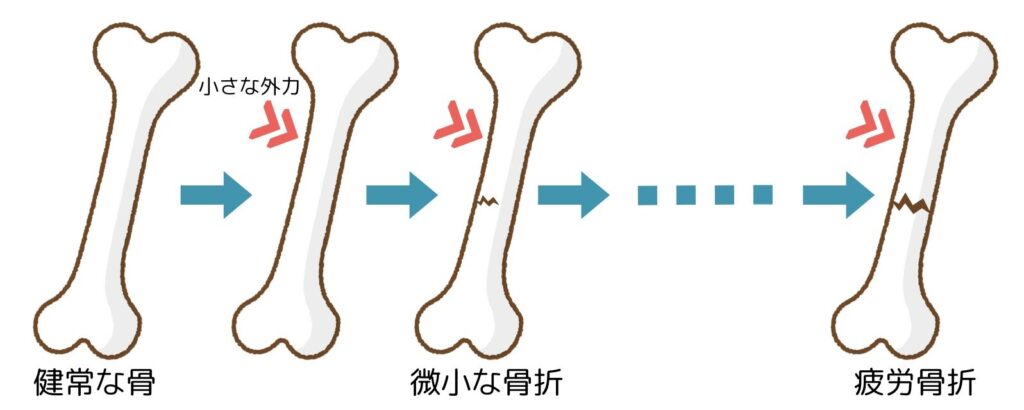

疲労骨折とは、1回の大きな力による通常の骨折とは異なり、骨の同じ部位に繰り返し加わる小さな力によって骨にヒビが入り、最終的には完全な骨折に至った状態をいいます。